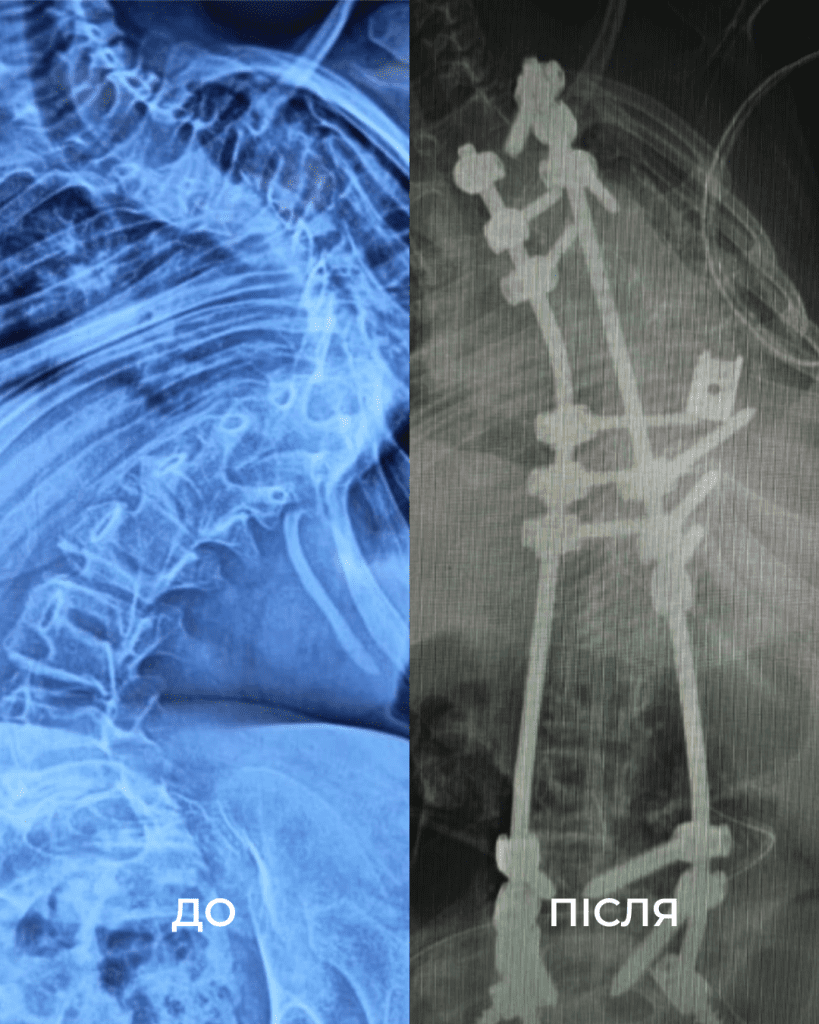

З роками стан лише погіршувався: невпинний біль, задишка, неможливість довго сидіти. Хребет дитини викривився аж на 160 градусів. Вдома дівчинка пересувалася з ходунцями, у школі – на кріслі колісному. Часто бувала в лікарнях та на реабілітації.

“Щоб виправити її сколіоз, нам потрібно було видалити цілий хребець. У перший день операції ми закріпили її хребет гвинтами. А потім уже на другий день видалили кілька ребер, ізолювали спинний мозок та встановили титанову клітку для підтримки хребта. А потім повільно виправляли її разом з моєю колегою, нейрофізіологинею Меган Маллані”, — розповідає американський ортопед-травматолог Марк Диржка.

Після двох операцій, 18 годин наркозу та через надто слабкі м’язи два наступні тижні Вікуся пробула в реанімації під киснем. Але результат того вартував. Хірургам вдалося вирівняти хребет дівчинки на 85%. Ось що каже мама Віки:

“Спина дійсно змінилася. Немає більше того горбу з ребер. Вона витягнулася, стала вища. Ми здивовані! І лікарі самі сказали, що зробили більше, ніж очікували”.